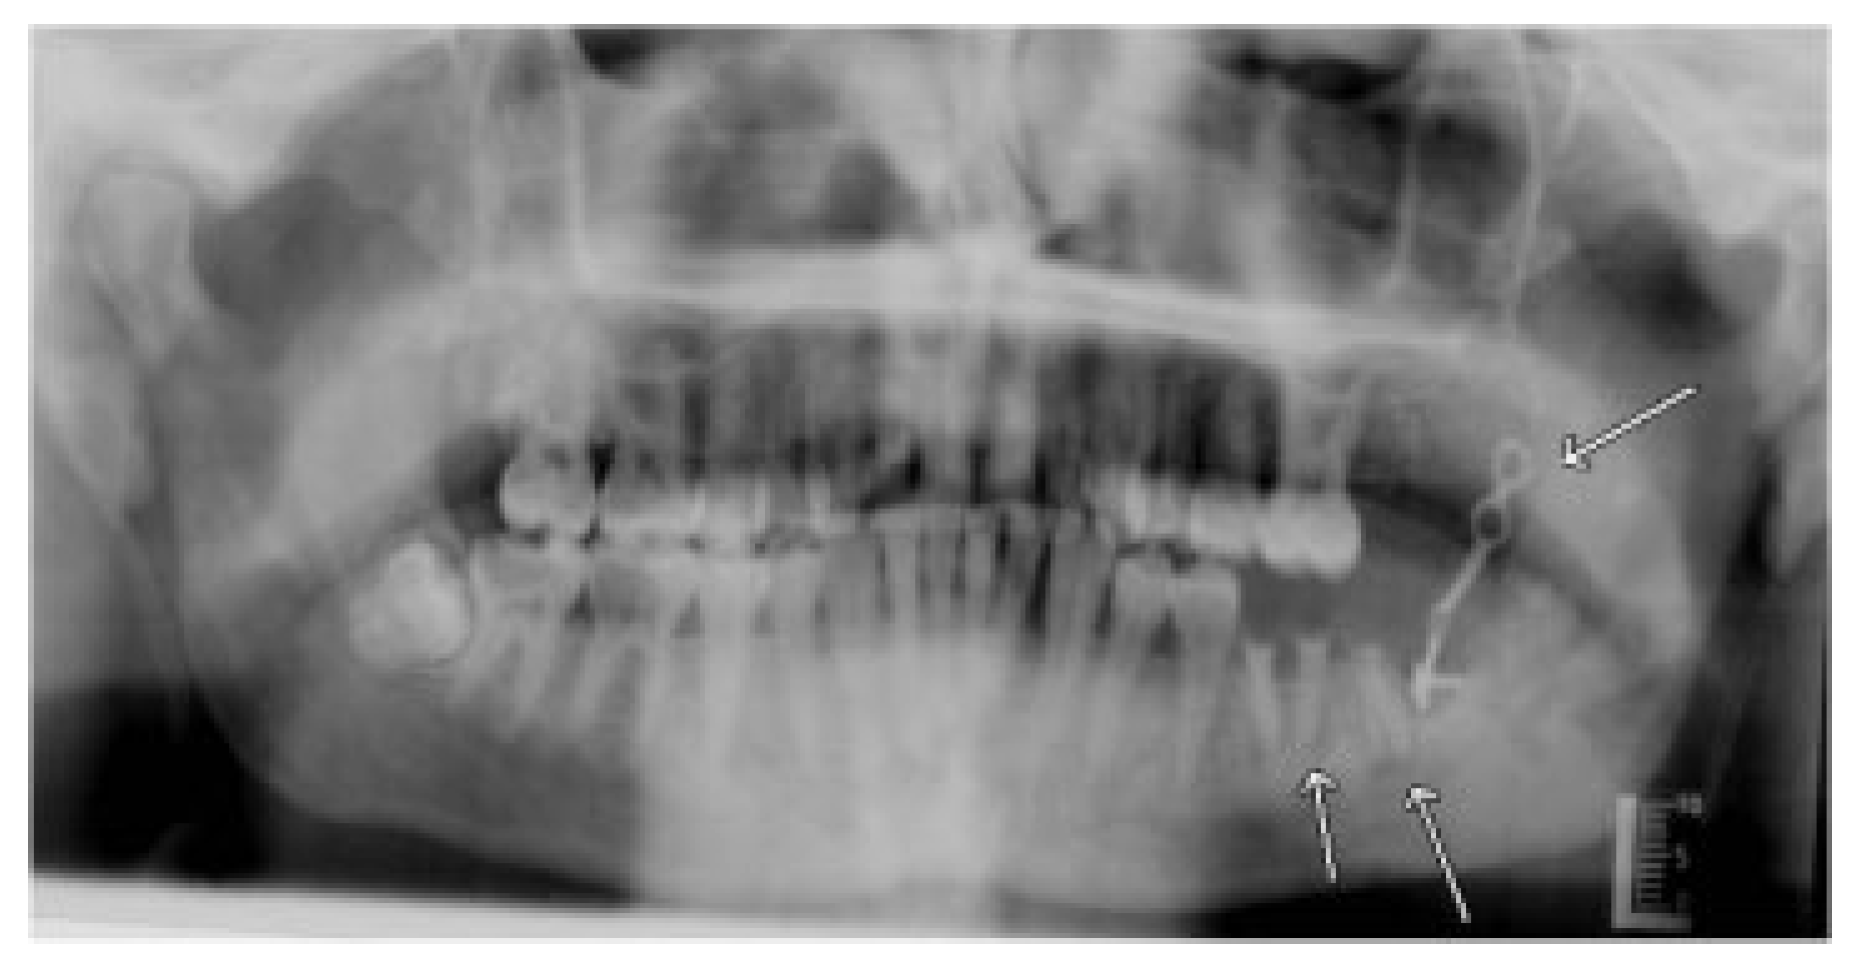

1.2. Surgical Technique

Strut Plate